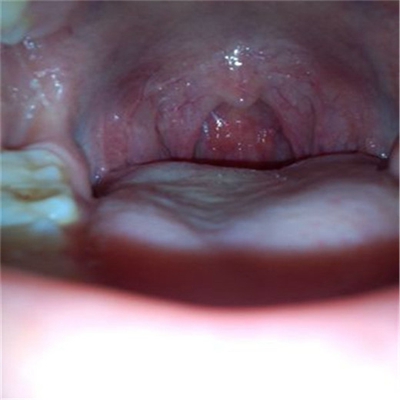

扁桃體惡性腫瘤圖片

扁桃體癌圖 (7)